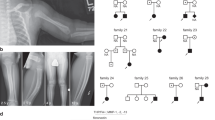

A three-year-old boy with partial distal 12q trisomy, 46,XY, der(9),t(9;12)(q34.3;q24.31)mat, is described. To our best knowledge, this is the second case in Japan. He has an arachnoid cyst, which has not yet been described in the literature.

Masuno, M., Fukushima, Y., Sugio, Y. et al. Partial distal 12q trisomy with arachnoid cyst. Jap J Human Genet 32, 39–43 (1987). https://doi.org/10.1007/BF01876526